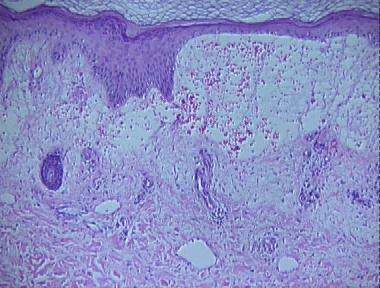

cellulitis

Histologic Features